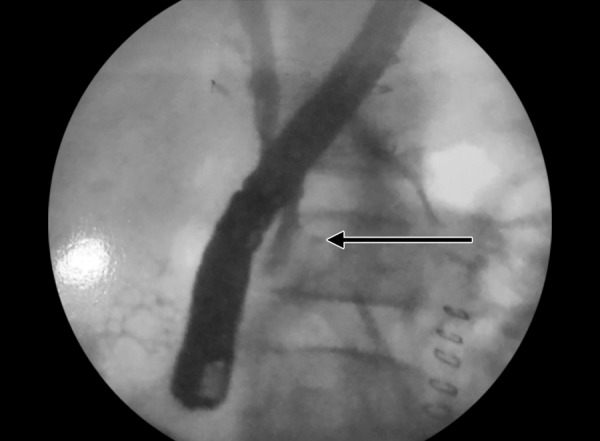

A 10-year-old girl was admitted in a private hospital for an acute abdomen. She presented with complaints of abdominal pain, distention, and fever. Preoperative ultrasound was suggestive of free fluid. Intraoperatively, there was bile in the peritoneal cavity, no bowel perforation and a rent in CBD, suggestive of biliary tract perforation. A drain was kept in the Morrison’s pouch, and she was referred to our institute for further management. At admission, the patient was stable in regard to hemodynamical parameters. The draining output was approximately 200 to 300 mL of bile per day. Contrast enhanced computed tomography (CECT) scan suggested discontinuity in the medial wall of suprapancreatic CBD extending proximally for a length of approximately 1.4 cm with an ill-defined collection in the Morrison’s pouch and mild free fluid in the peritoneal cavity (Fig. 1). Endoscopic retrograde cholangiopancreatography revealed a leak from CBD just below the insertion of cystic duct (Figs 2 and 3), and a 7 French stent was inserted with the tip beyond the leak. The abdominal draining was stopped and removed. The patient was gradually shifted to oral diet. She was discharged after 8 days, and her stent was removed after 8 weeks. She is doing well on follow-up.